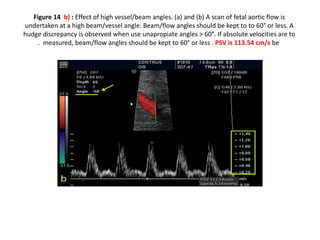

Figure 8 : B Setting the color gain : decreased to 35 so to minimize the signals

(artefacts) from surrondng tissue

Figure 8 :B Setting the color gain : decreased to 35 so to minimize the signals (artefacts) from surrondng tissue